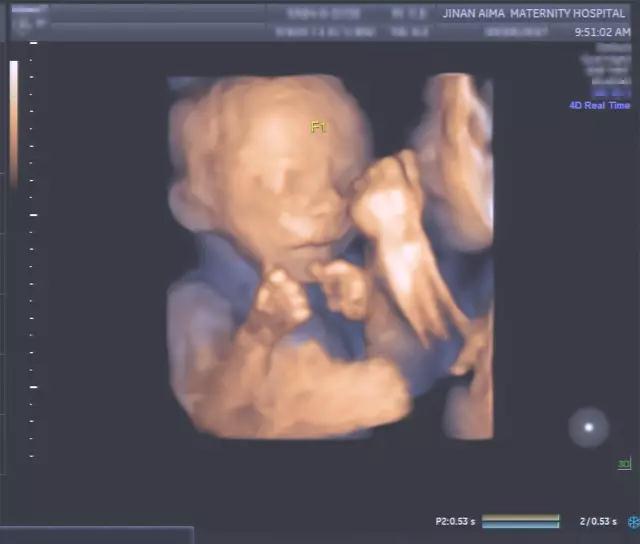

在艾玛妇产四维彩超室

我们看到这样系列

让人“惊讶”的四维彩超(四维彩超)资料

双胞胎宝宝在妈妈的子宫里

是这样“玩耍”的

对双胞胎宝宝面对面

像是在说“悄悄话”

这个温馨的画面

就发生在妈妈的子宫里

被四维彩超记录了下来

通过四维彩超

能看到双胞胎宝宝互相推挤的胎儿图像

比如双胞胎或三胞胎在子宫里

边抓着对方的手和脸

边互相推挤的过程